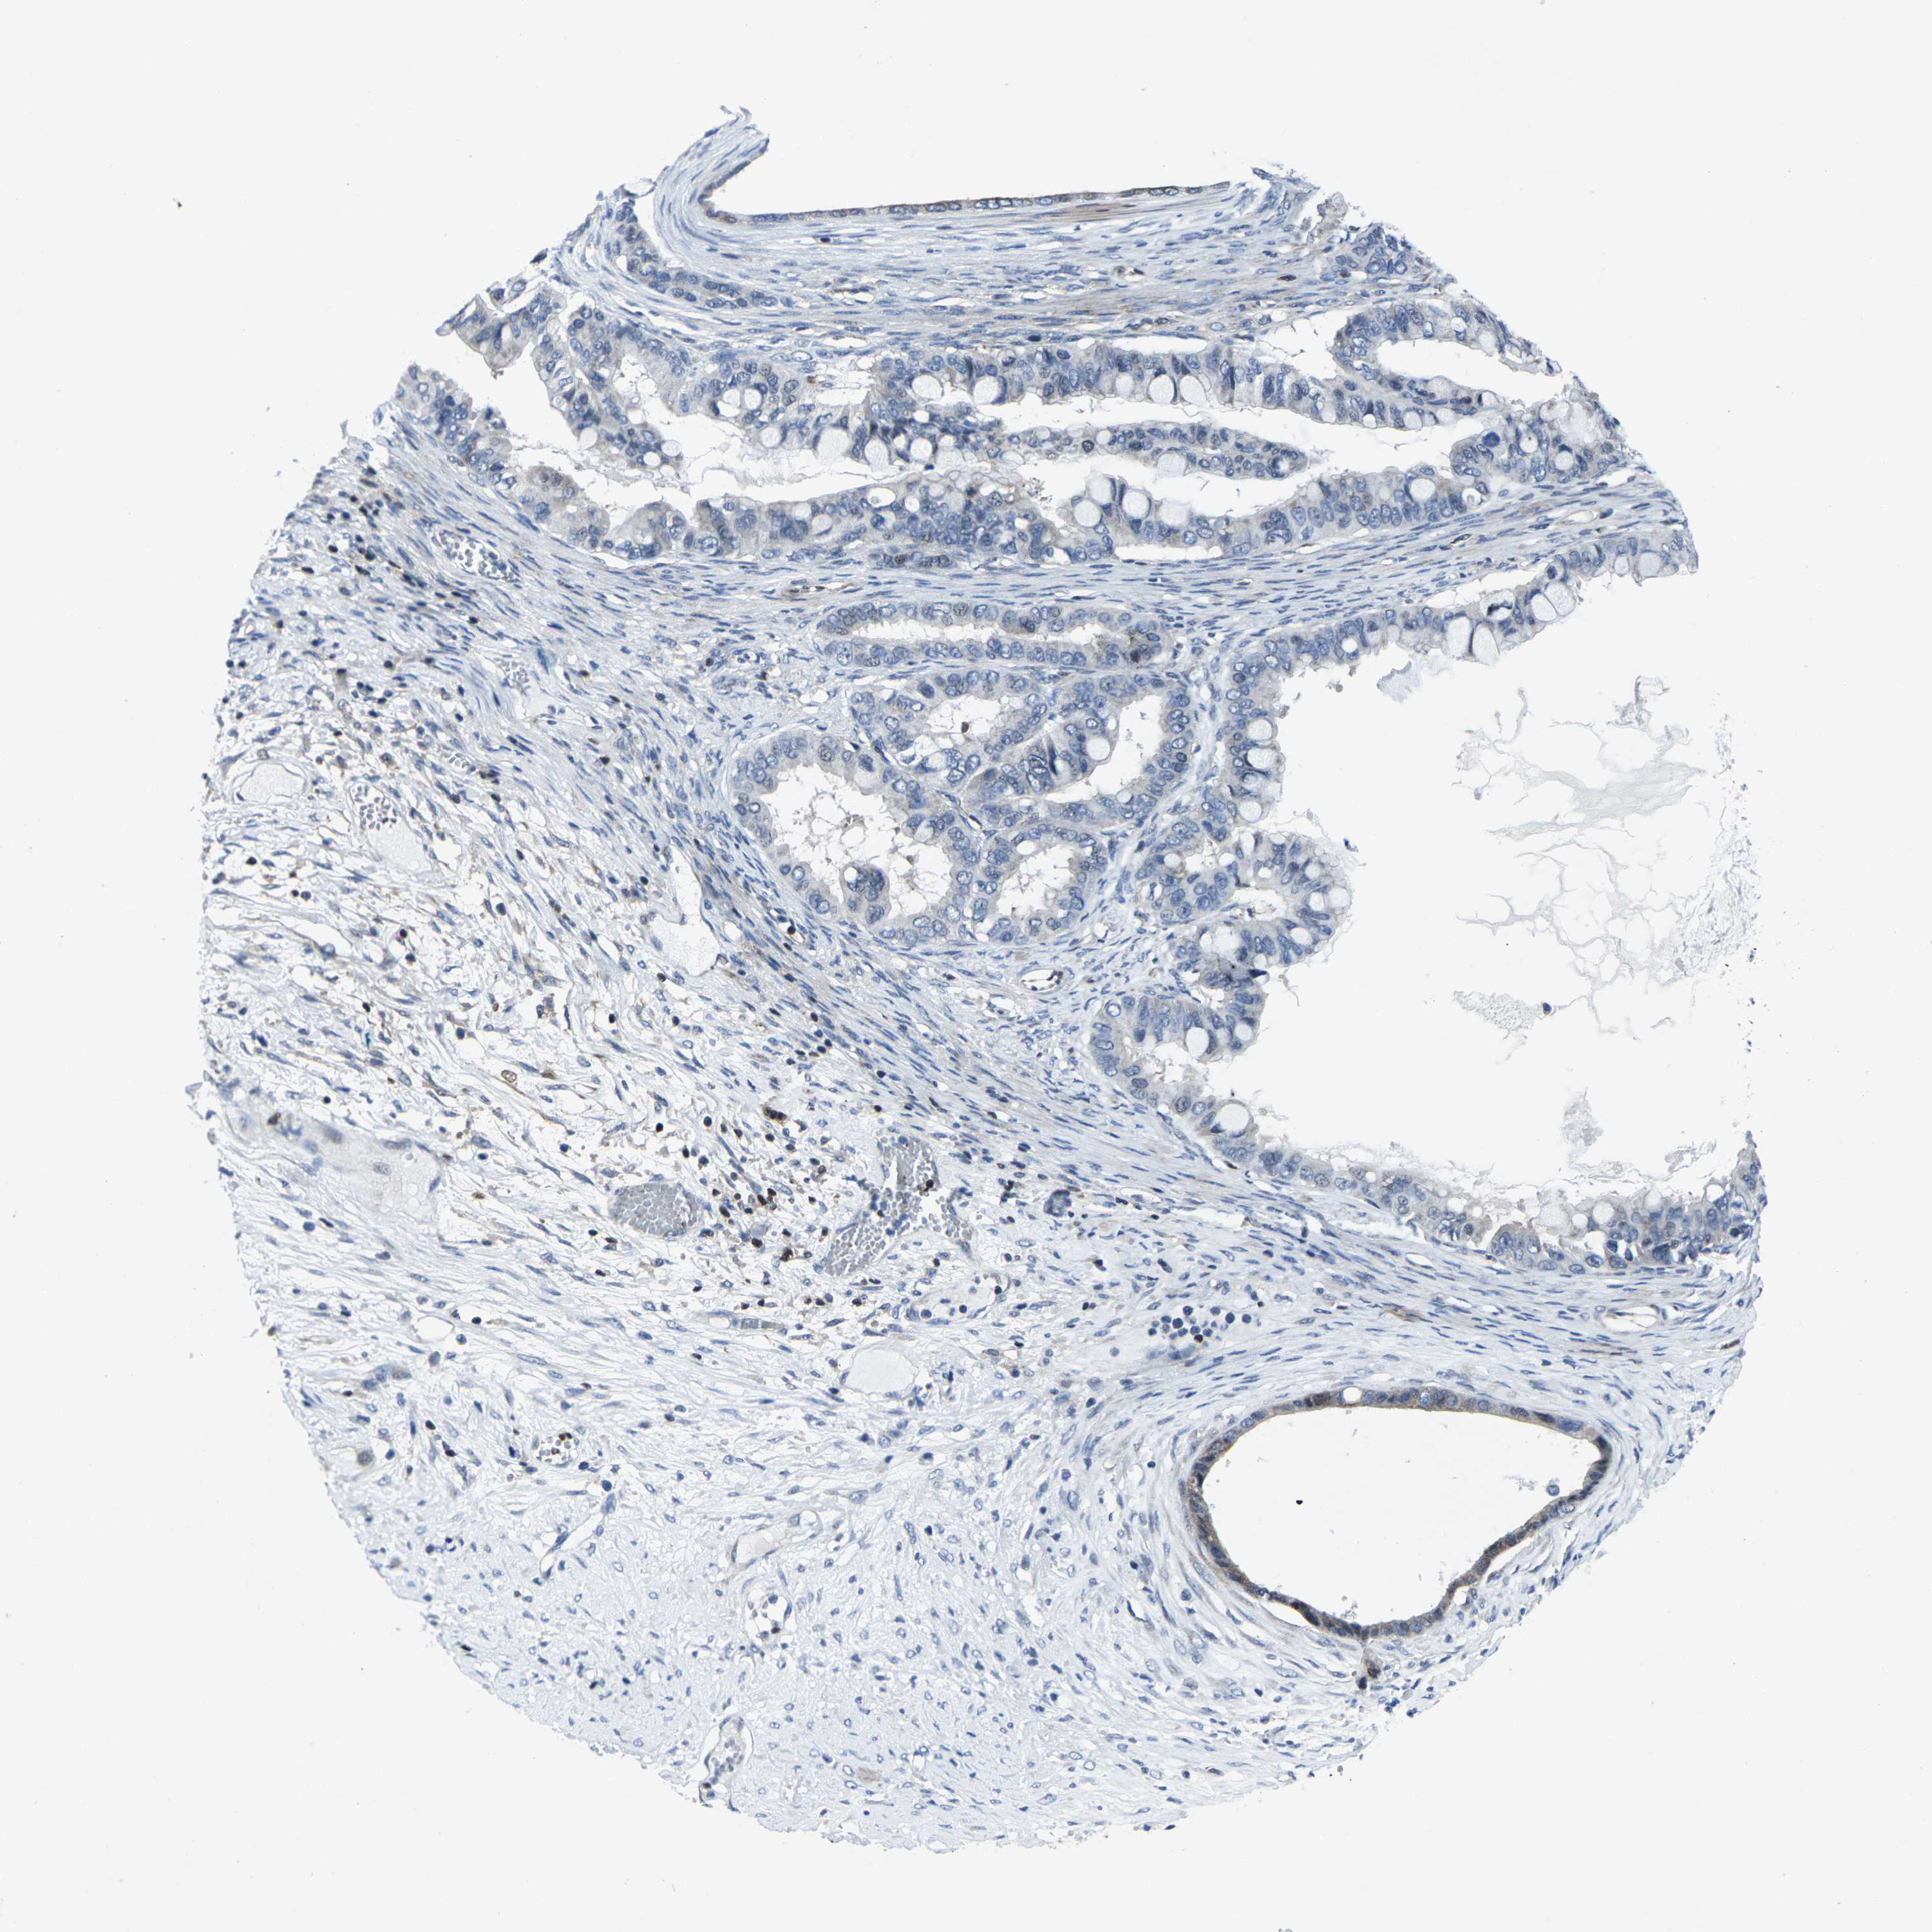

OVARIAN CANCER - Protein expressioni

A mouse-over function shows sample information and annotation data. Click on an image to view it in a full screen mode. Samples can be filtered based on level of antibody staining by selecting one or several of the following categories: high, medium, low and not detected. The assay and annotation is described here.

Note that samples used for immunohistochemistry by the Human Protein Atlas do not correspond to samples in the TCGA dataset.

Antibody stainingi

Antibody staining in the annotated cell types in the current human tissue is reported as not detected, low, medium, or high, based on conventional immunohistochemistry profiling in selected tissues. This score is based on the combination of the staining intensity and fraction of stained cells.

Each image is clickable and will lead to virtual microscopy that enables deeper exploration of all samples and also displays staining intensity scores, fraction scores and subcellular localization as well as patient and tissue information for each sample.

Antibody HPA001860

Antibody CAB013108

Cystadenocarcinoma, serous, NOS

Cystadenocarcinoma, mucinous, NOS

Carcinoma, endometroid

Carcinoma, NOS